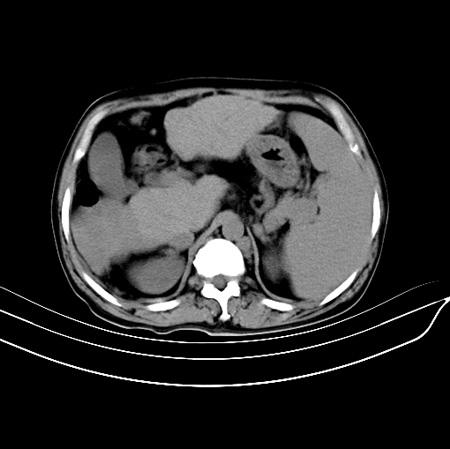

以下是引用江尾海头在2007-9-7 19:01:00的发言:[br]肝叶比例失调,肝边缘高低不平,尾状叶增大,肝裂增宽。肝右叶见较大密度减低影,边缘欠清。脾脏明显增大,胃底及奇静脉半奇静脉曲张。胆囊未见明显显示。 考虑:1、肝癌。2、肝硬化伴脾大静脉曲张。

以下是引用zhangxu5888在2007-9-7 22:31:00的发言:[br]1、肝硬化,食管 胃底及奇静脉半奇静脉曲张;2、脾脏肿大; 3、肝右叶的病灶呈锲性改变,内可见条片状钙化,边界清晰,密度明显低于周围正常肝组织,我觉得肝癌可能性不是很大, 同意楼上观点,有可能是栓塞,建议增强.